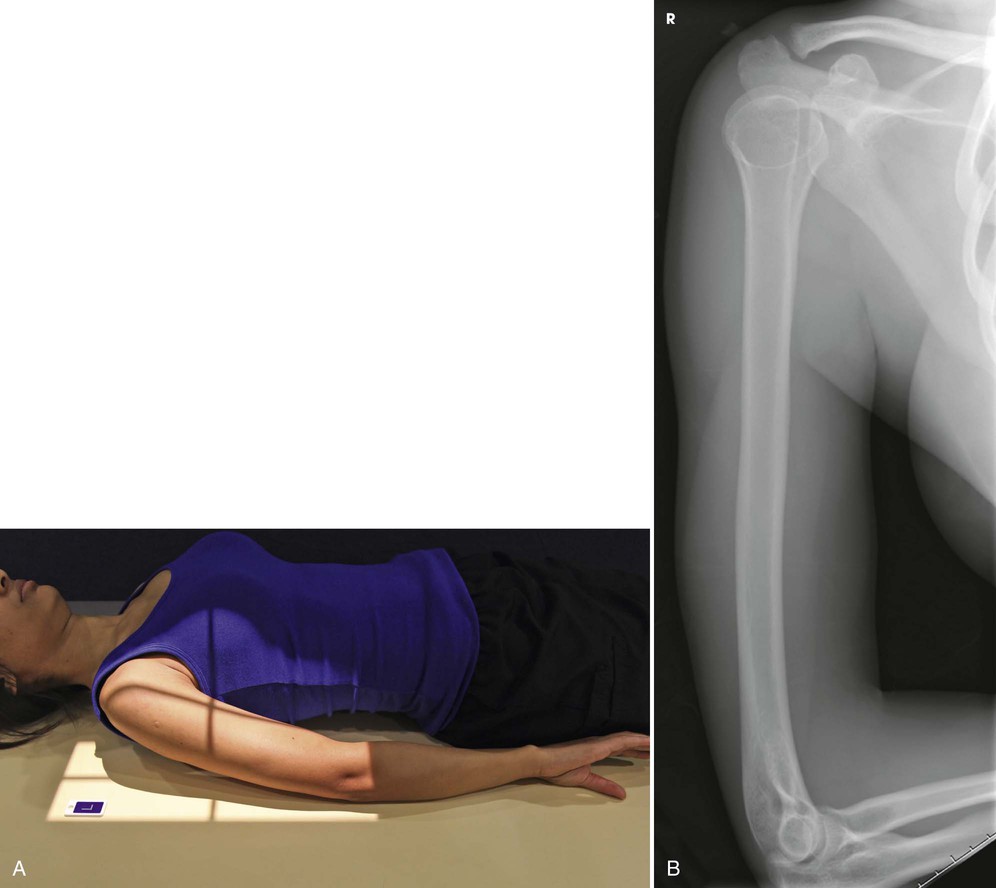

Lateromedial

Recumbent

Position of part

• Adjust the top of the IR to be approximately

inches (3.8 cm) above the level of the head of the humerus.

• Unless contraindicated by possible fracture, abduct the arm and center the IR under it.

• Rotate the forearm medially to place the epicondyles perpendicular to the plane of the IR, and rest the posterior aspect of the hand against the patient's side. This movement turns the epicondyles in the lateral position without flexing the elbow (see Fig. 4-153). (The elbow may be flexed slightly for comfort.)

• Adjust the position of the IR to include the entire length of the humerus (Fig. 4-157).

Structures shown

The lateral projection shows the entire length of the humerus. A true lateral image is confirmed by superimposed epicondyles (see Fig. 4-157).